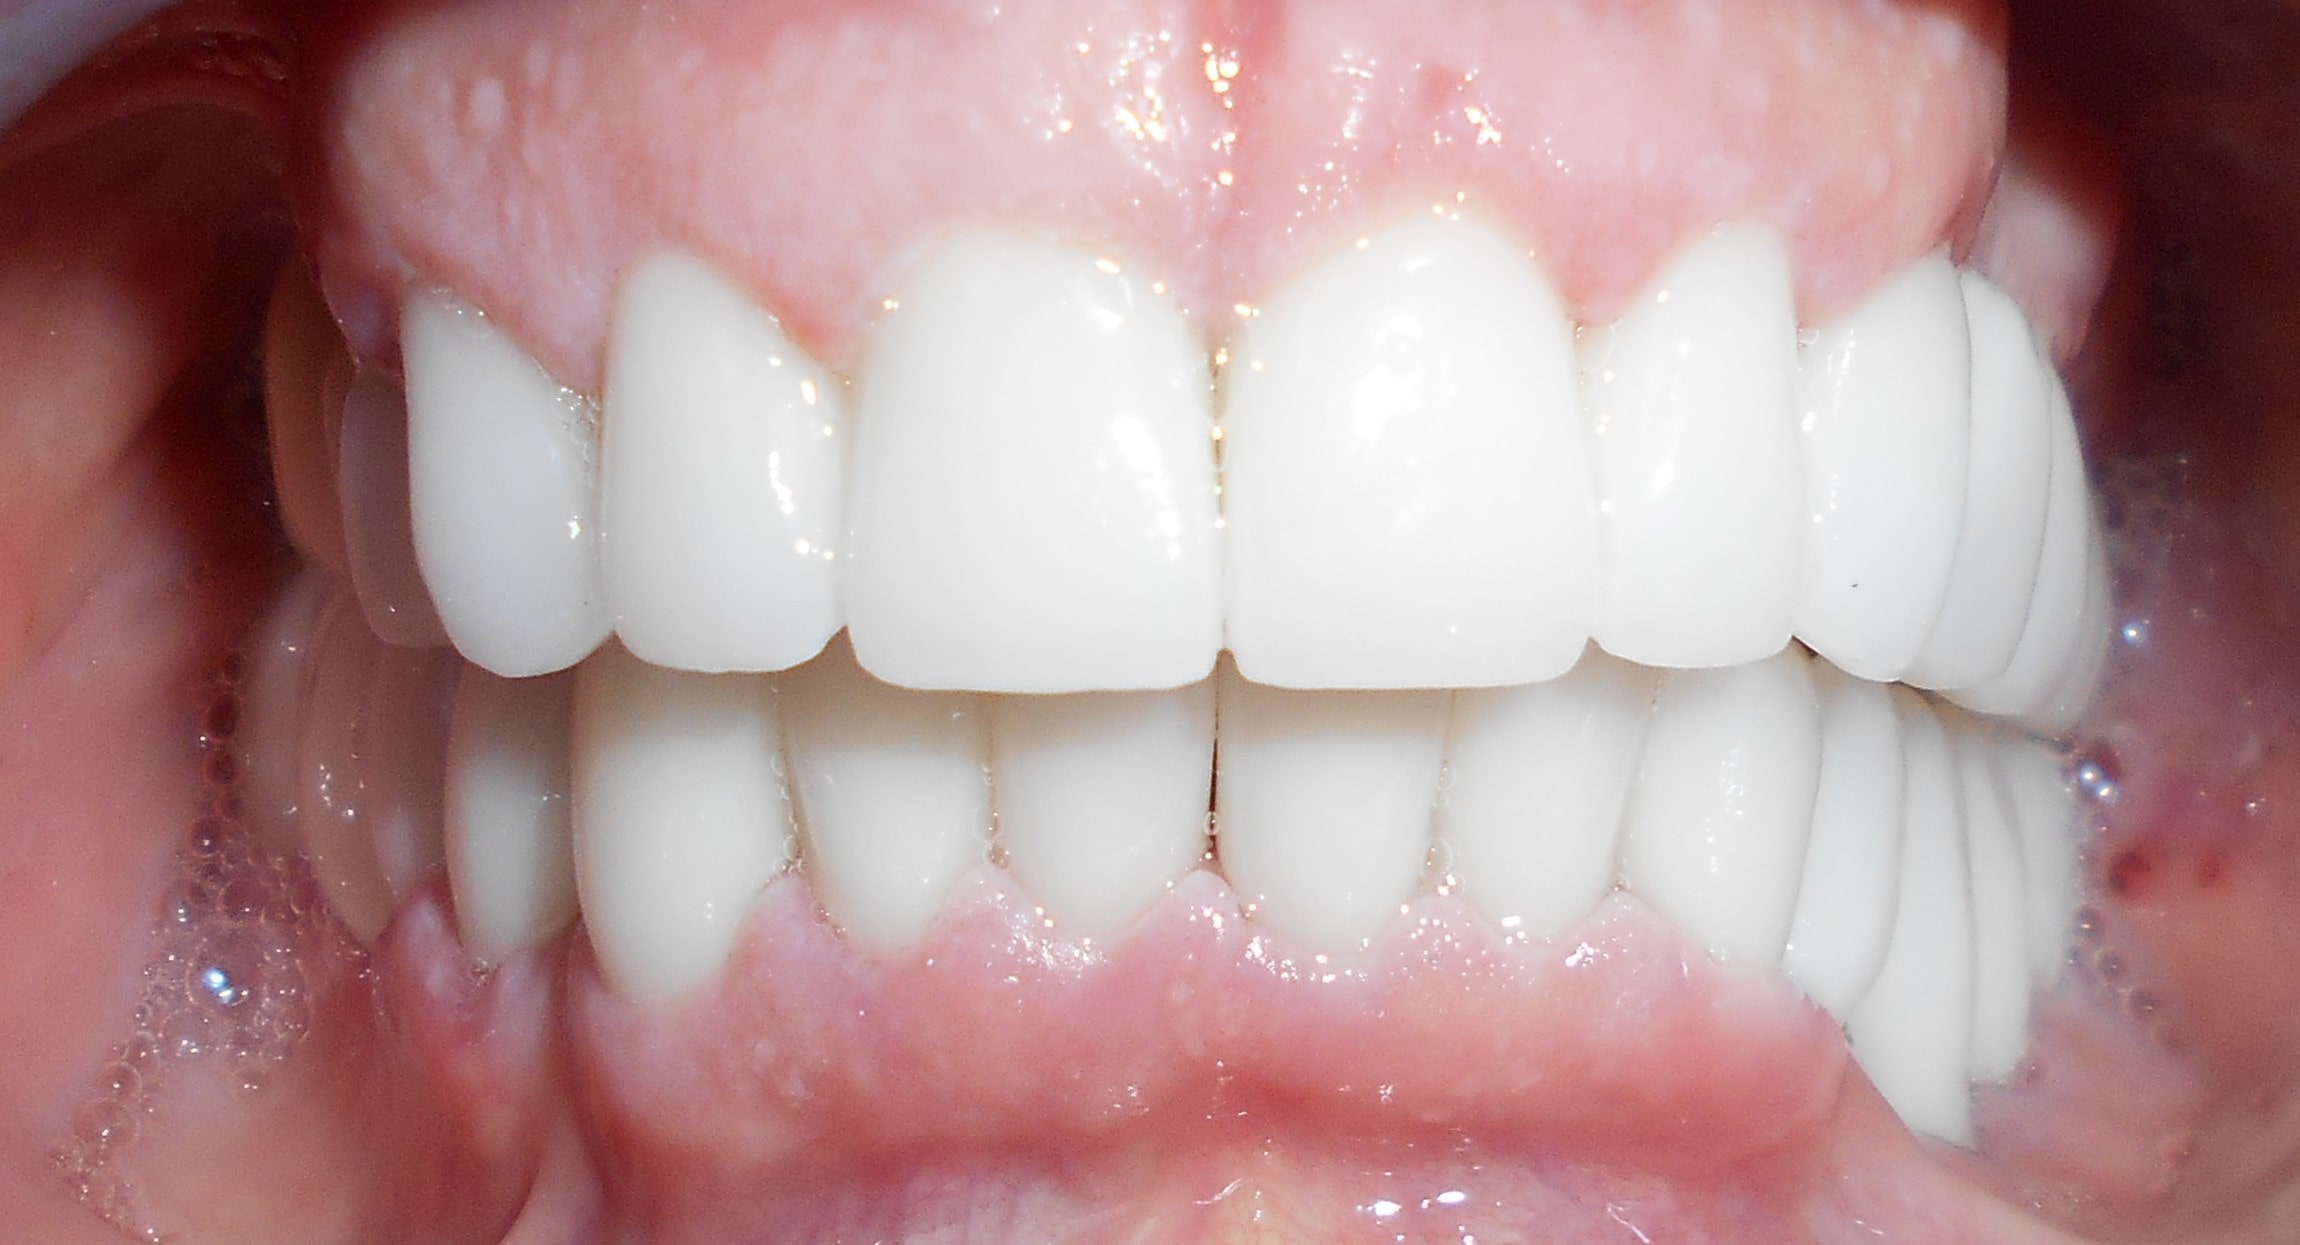

Pacijent 3

Pacijent dolazi sa starim mostovima i izraženom parodontopatijom u donjoj vilici. Urađeno je skidanje postojećih mostova i istovremena ekstrakcija svih parodontopatičhin zuba uz ugradnju sedam implantata u gornjoj vilici i pet implantata u donjoj vilici. Pacijent je nakon tri dana bio privremneo protetski zbrinut sa fiksnim privremeni krunicama koje su fiksirane na tek ugrađenim implantaima. Nakon četiri meseca je izrađen fiksni cirkonijum kermički- bezmetalni most u gornjoj i donjoj vilici. Rad uspešno završen pre tri godine.